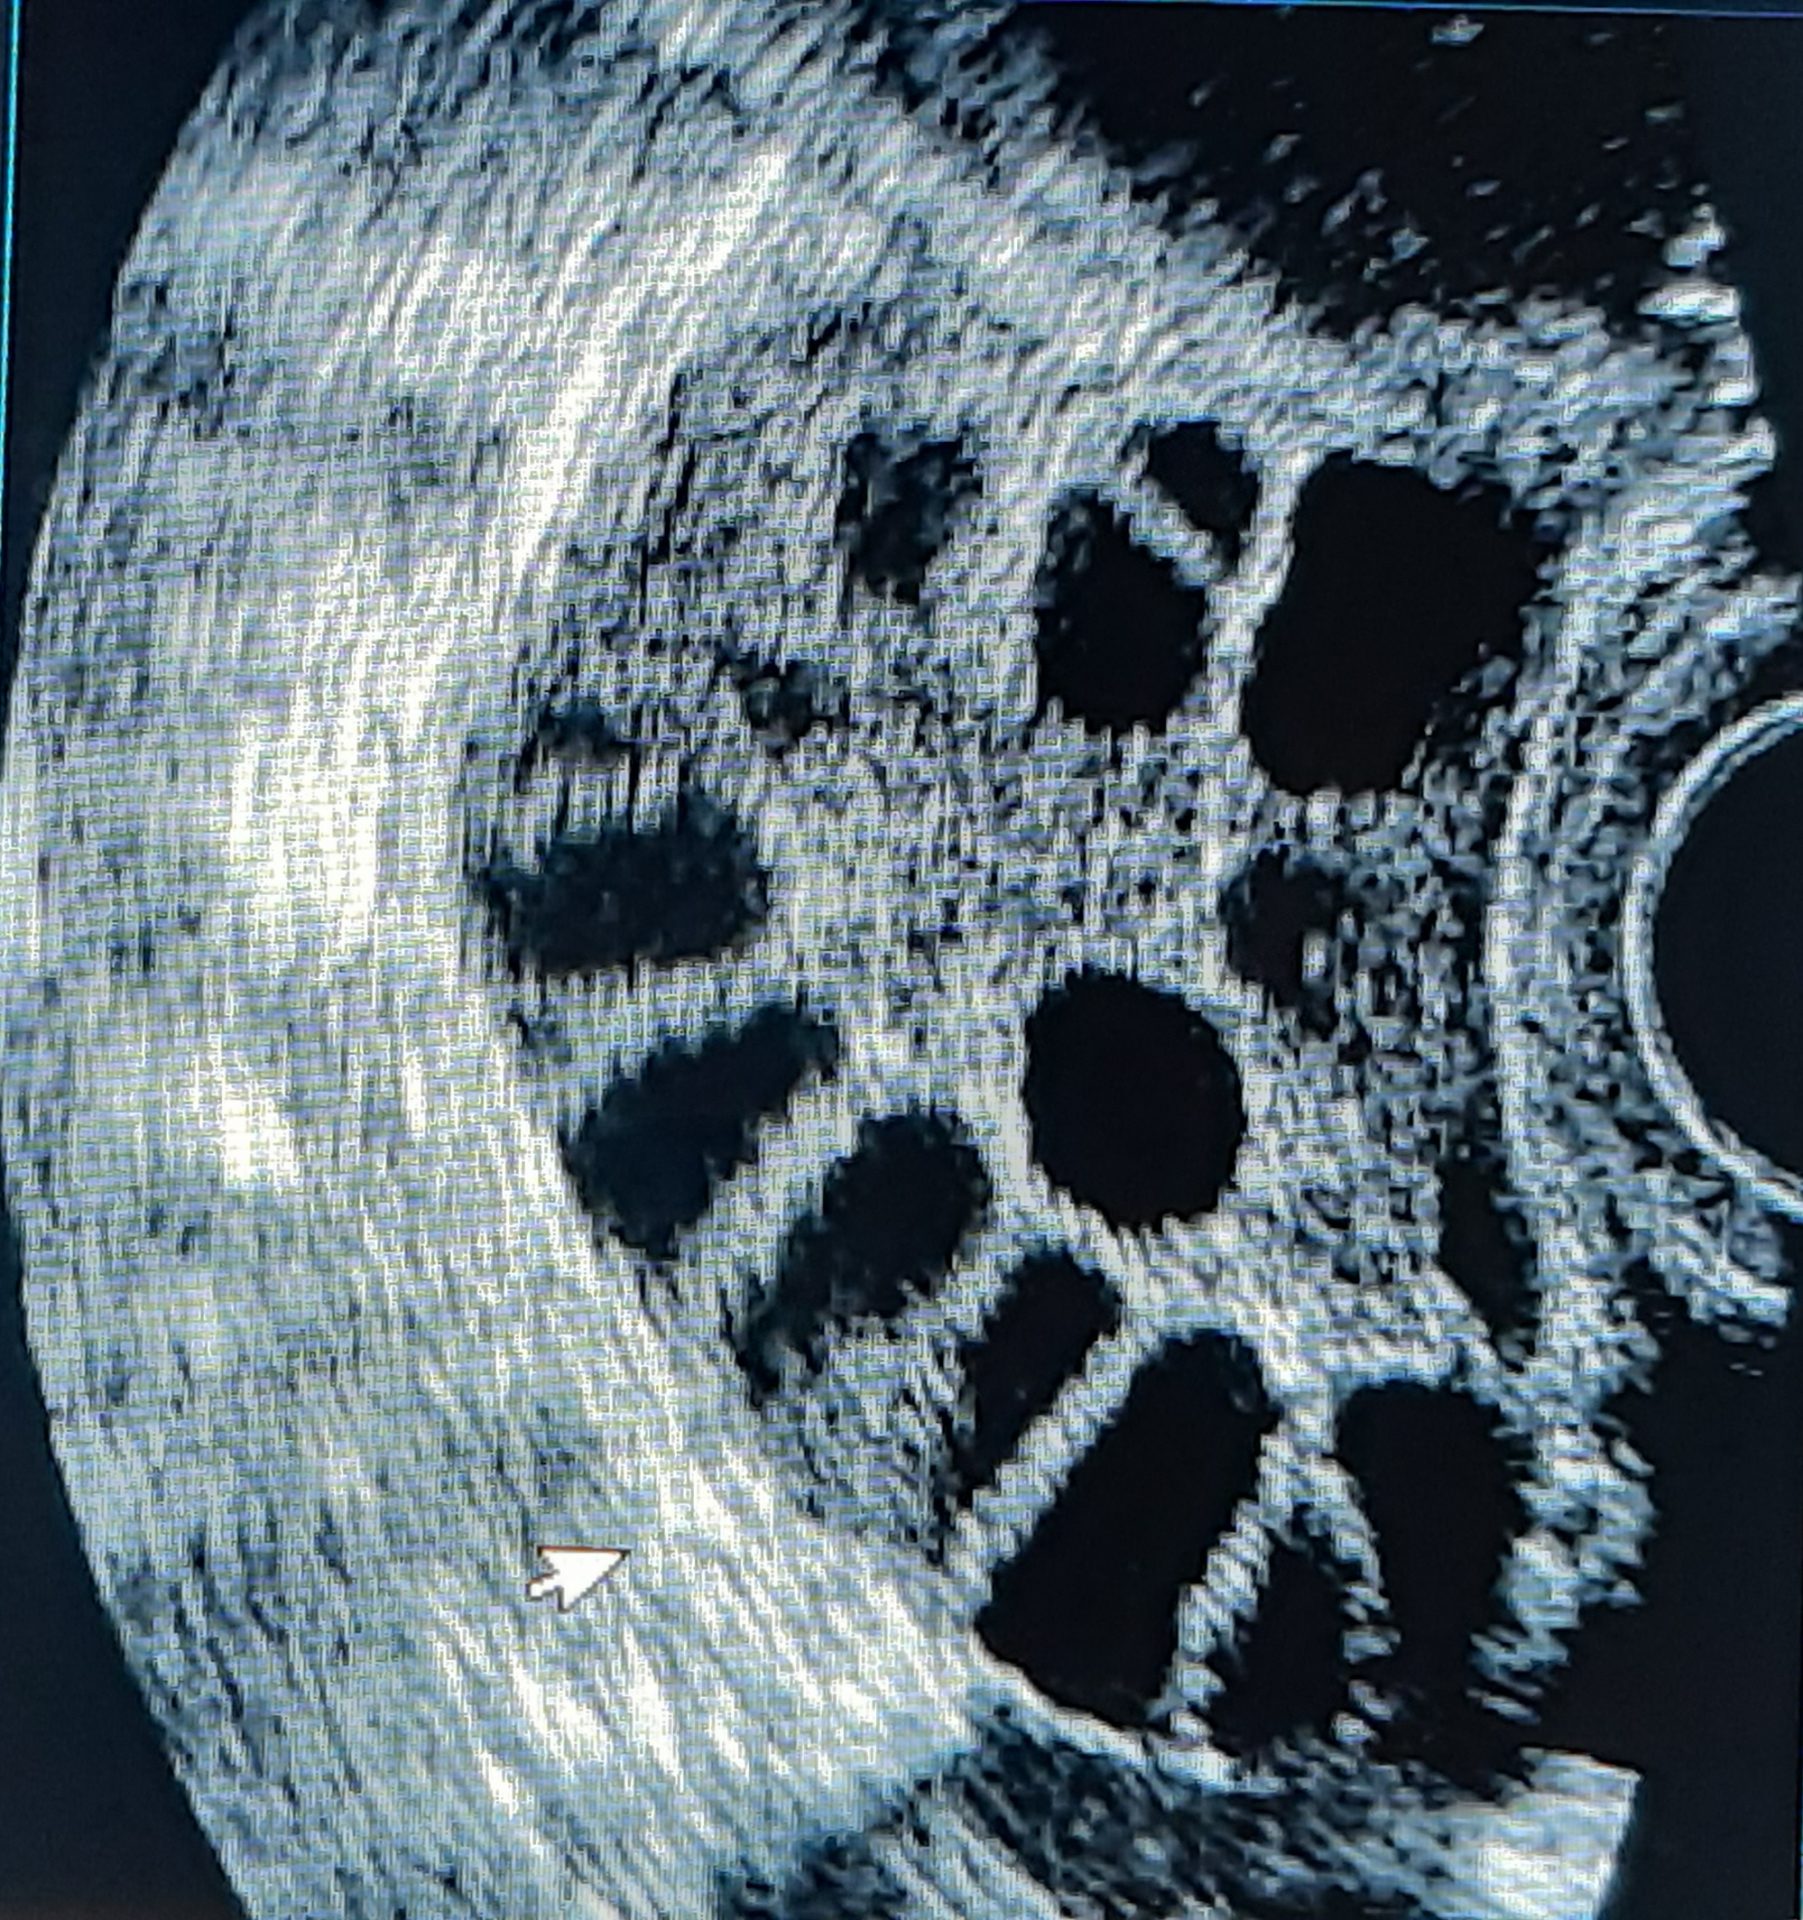

El síndrome de ovarios poliquísticos consiste en la aparición de varios pequeños quistes en el interior de los ovarios, lo cual es causado por una pérdida en el equilibrio hormonal a expensas de hormonas masculinas (andrógenos), los cuales dificultan que los ovarios liberen óvulos maduros que le permitan a la mujer alcanzar su periodo fértil del mes.